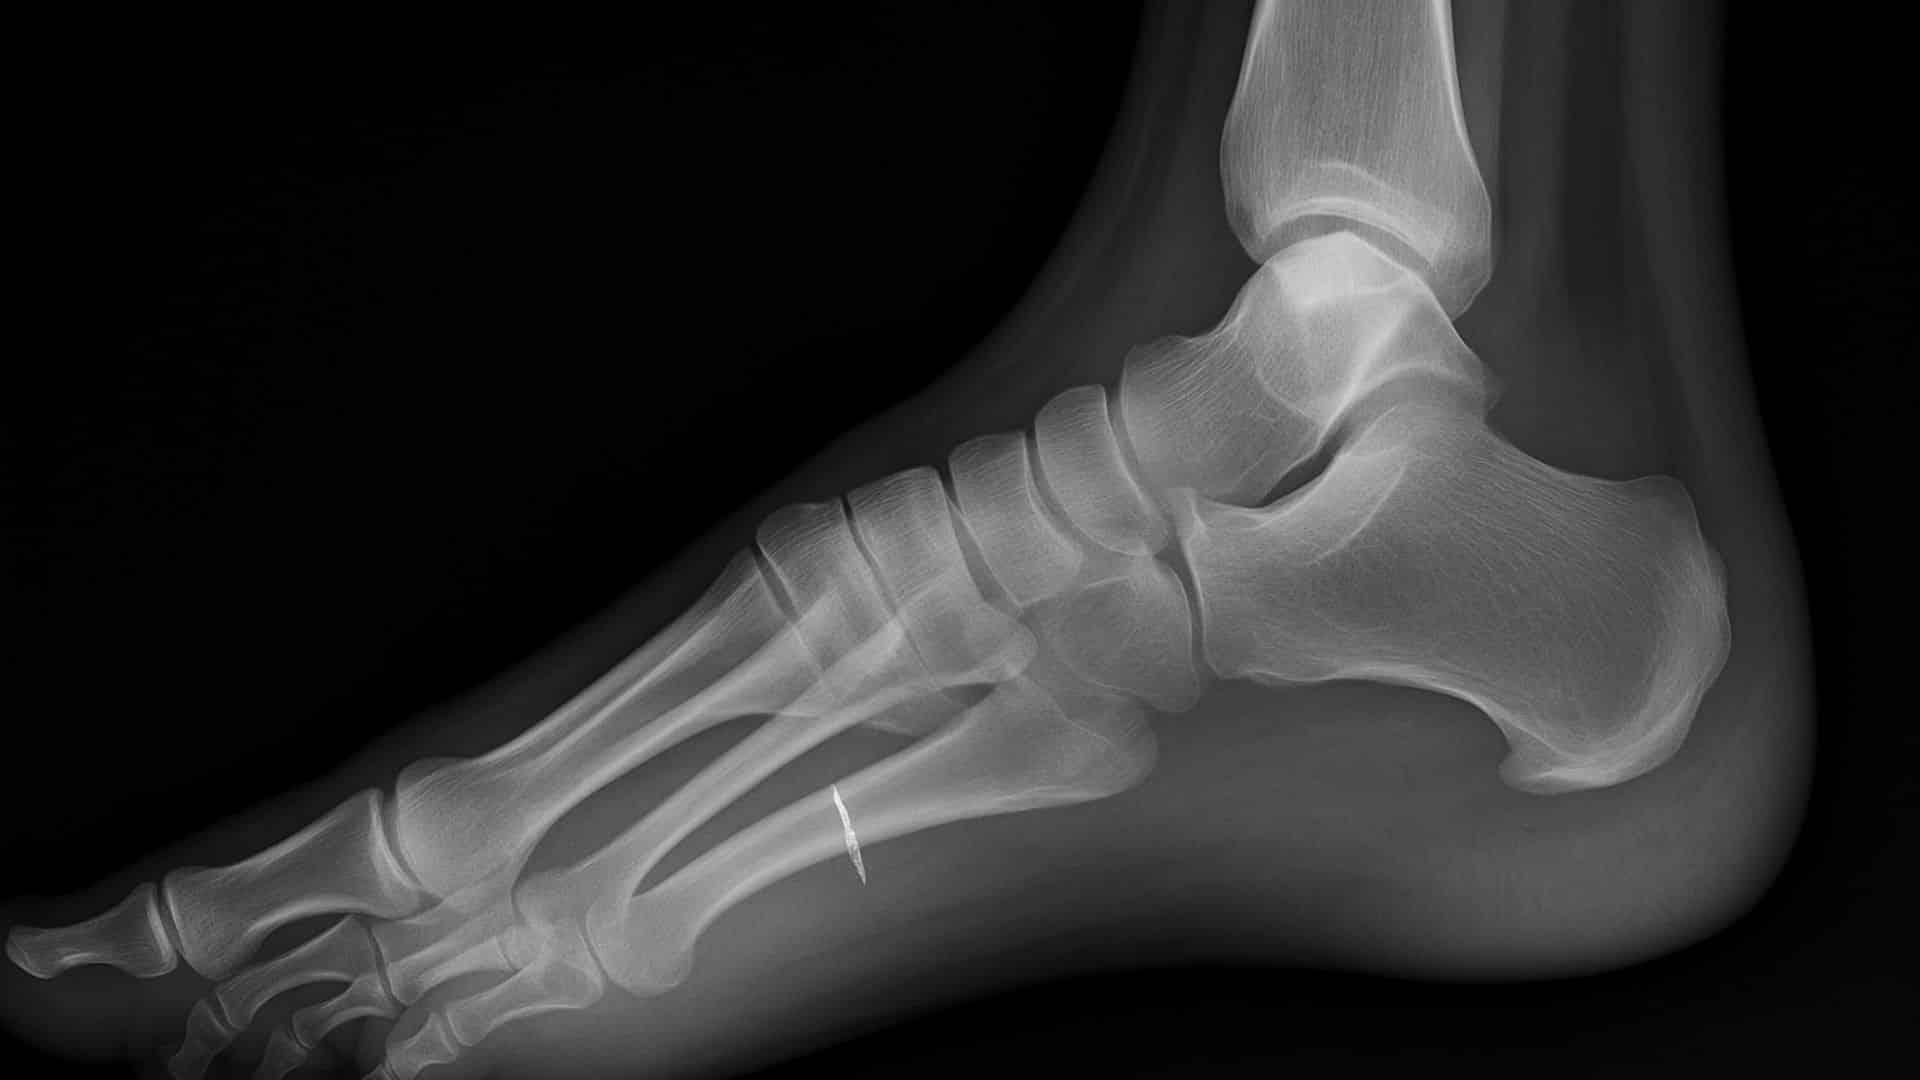

15. Stress Fractures

Tiny cracks develop in foot bones from repetitive force or overuse. These are common in weight-bearing bones and are more likely in older adults with weakened bones or vitamin D deficiency.

Pain from stress fractures starts gradually and worsens with activity. The second and third toe bones are most commonly affected.

Quick Fix: Rest from Weight-Bearing Activities and Wear Protective Boots.